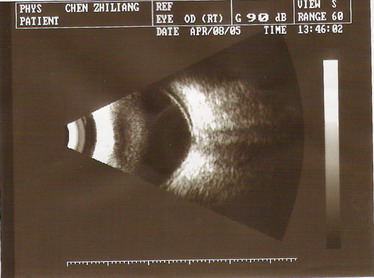

2005年4月8日B超:右眼玻璃体轻度混浊,右眼视网膜脱离,视盘凹陷(青光眼型)

2003年9月16日B超:双眼玻璃体轻度混浊,右眼视网膜脱离

2003年11月12日B超:右眼玻璃体轻度混浊,右眼视网膜脱离

2004年3月2日B超:右眼视网膜脱离(鼻上)